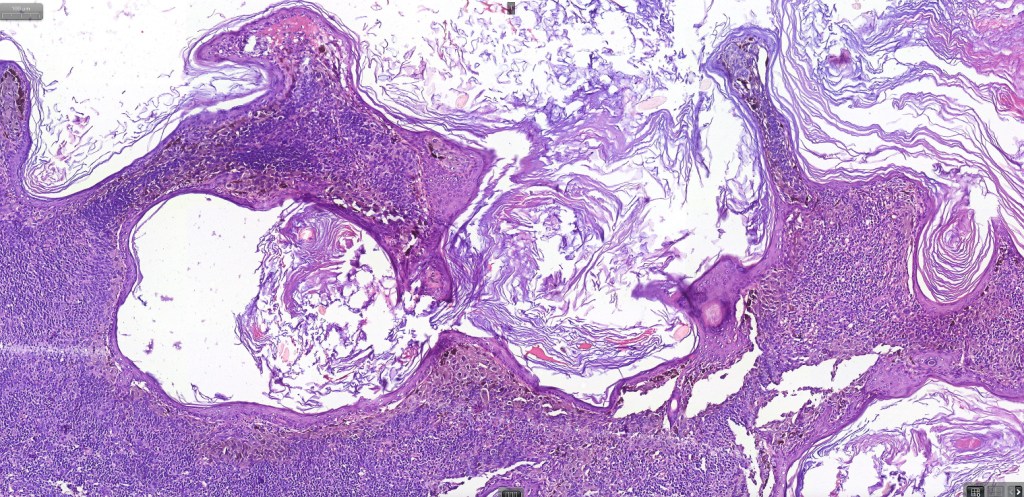

Although most scalp nevi can be readily classified into the regular nevus subtypes- common, congenital, blue etc, exceptionally they may show features more commonly seen at “the socalled milk-line” sites. Some authors use the term “atypical nevus of the scalp”.

Histological features

•Junctional/compound

•Large dyscohesive nests with retraction artifact, not restricted to the tips of the epidermal ridges

•Heavy pigmentation (sometimes gray/green)

•Bridging common, often over multiple rete ridges

•Variable atypia (can be marked)

•Central pagetoid spread

•Superficial dermal atypia

•Junctional mitoses sometimes present, dermal mitoses+/-, can be multiple but never atypical

•Dermal fibrosis (sometimes lamellar)

. HMB45 shows gradation with depth, Ki67 is low